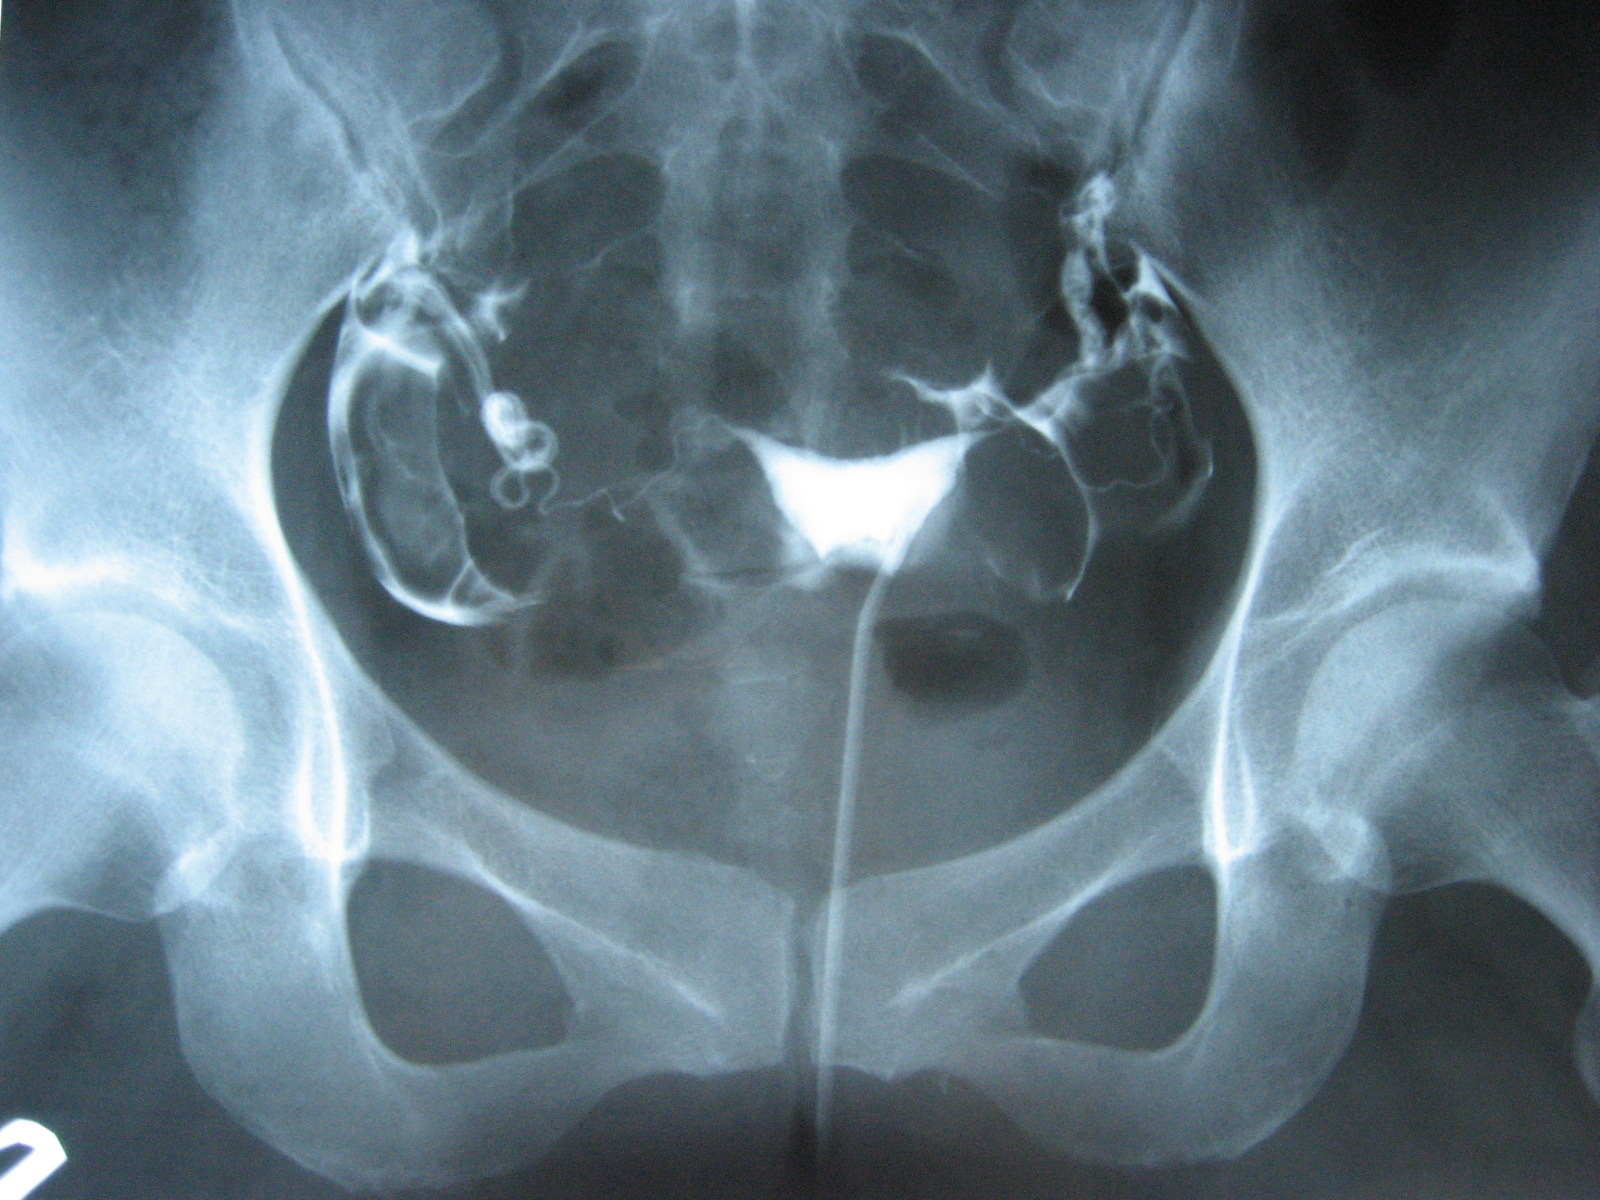

<자궁난관조영술(HSG) 사진>

자궁난관조영술은 X-ray를 이용한 검사로 자궁강을 진찰하고 양쪽 난관이 열려 있는지 확인하기 위해 시행됩니다. 본 검사는 불임의 잠재적 원인들을 확인하기 위해 주로 시행되는데 자궁강과 난관의 모양 뿐만 아니라 폐색이나 유착과 같은 기능적인 평가도 가능합니다.

처음에는 골반 진찰이 시행되고 질경을 자궁경부를 볼 수 있도록 질로 삽입됩니다. 기구가 자궁경부에 위치하고 그리고 나서 작은 관이 자궁경부가 열리는 바깥쪽에 위치하게 됩니다. 이 관을 통해서 요오드로 이루어진 조영제가 자궁 강으로 주입됩니다. 이때, 자궁강과 양쪽 난관으로 조영제가 주입되는 과정은 X-ray를 이용한 촬영으로 확인합니다. 일반적으로 이 검사는 4~5분 안에 완료가 됩니다. 검사로 인해 약간의 복통을 일으킬 수 있으나 검사가 완료가 이후에는 점차 사라집니다.